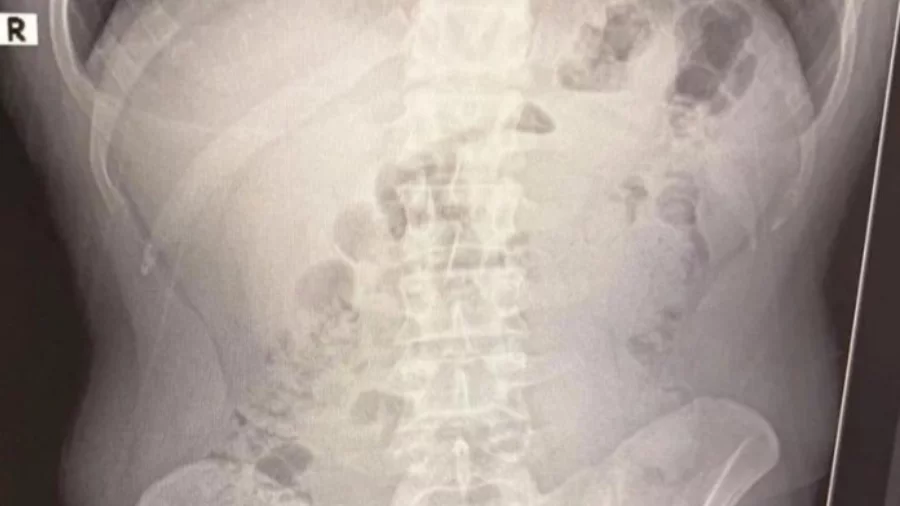

Қўлга олинганлар тиббий кўрик учун шифохонага олиб кетилган. Рентген текшируви натижасида уларнинг ошқозонида метамфетамин капсулалари борлиги фош этилган. Суд Эрон фуқароларини ҳибсда сақлашга қарор чиқарган.